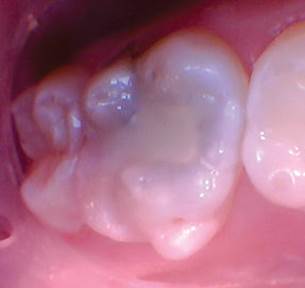

Caso 1

Un paciente de 8 años presentó descomposición de OD en un primer molar primario con síntomas de pulpitis reversible. El diente fue el tratamiento planificado para una restauración de OD con Activa Bioactive Restorative (Pulpdent). Tras la excavación por descomposición, se produjo una exposición pulpar que requirió una pulpotomía terapéutica. Debido a la edad del paciente, me sentí cómodo con una pulpotomía terapéutica con Biodentine (Septodont) seguida de una restauración estética. Si el paciente hubiera tenido entre cuatro y cinco años, me habría restaurado con una corona de acero inoxidable debido a su historial comprobado de longevidad.

Figura 1 Vista preoperatoria del primer molar primario superior. |